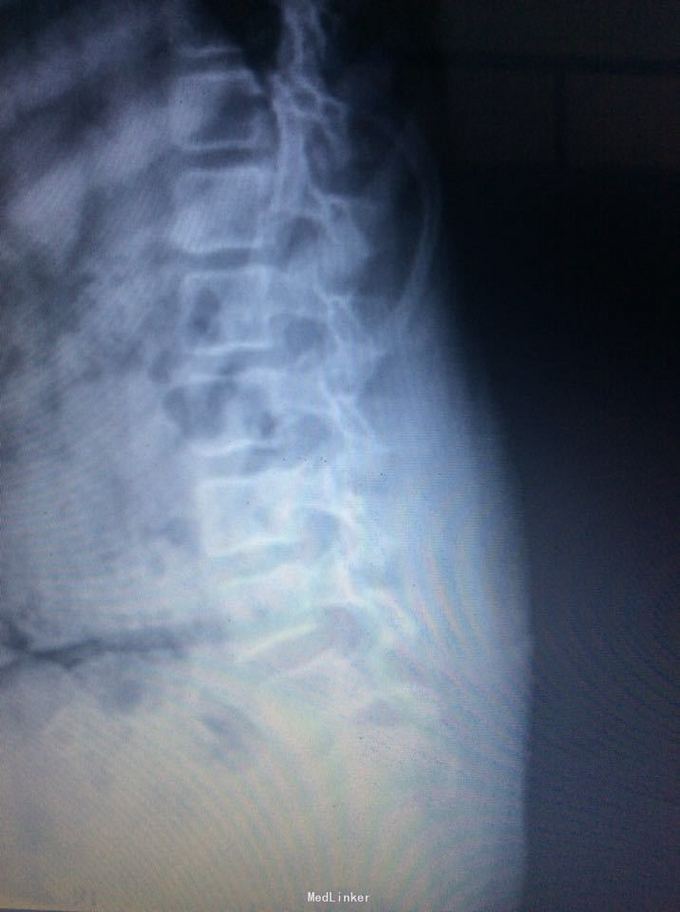

腰椎滑脱

椎体滑脱

9岁,腰痛一年

腰5椎体滑脱ii度 后路椎弓根钉椎间自体髂骨融合